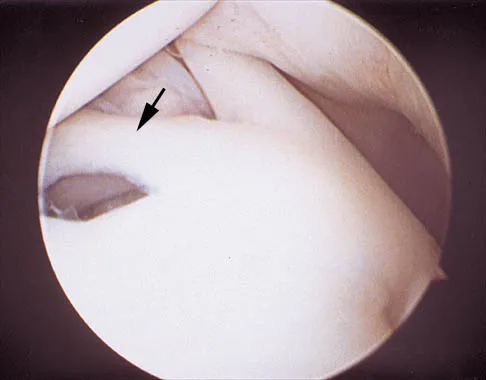

A 24-year-old athlete has a painful right shoulder. Figure 30 shows an intra-articular photograph that was obtained through a posterior portal during arthroscopy; the labrum is indicated by the arrow. Based on these findings, management should consist of

Explanation